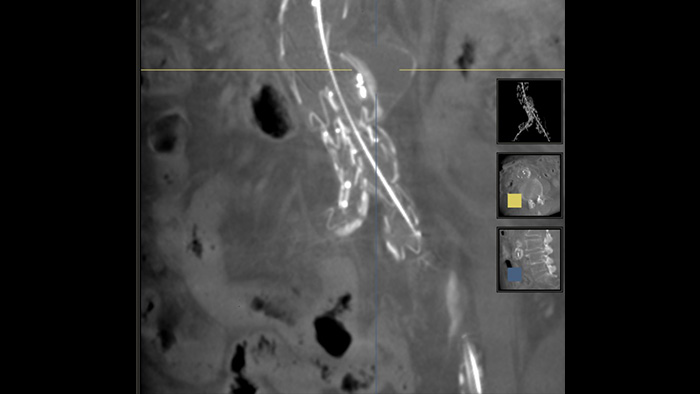

SmartCT Soft Tissue es una técnica de adquisición de rayos X que genera una visualización similar a una TC de tejido blando en relación con otras estructuras durante los procedimientos, todo controlado a través de la pantalla táctil en la mesa. Puede utilizar las imágenes similares a la TC para evaluar el tejido blando, la estructura ósea y la implementación del stent antes, durante y después de los procedimientos de intervención. Esta técnica es particularmente útil para comprobar si hay complicaciones después de procedimientos (complejos) de reparación endovascular de aneurismas (REVA).